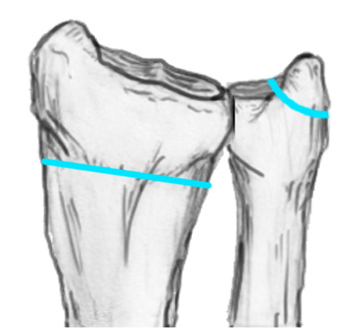

Distal Radius Angles

- radial volar tilt 11°

- radial inclination 22°

- radius is 11 mm longer than ulna

- ulna variance 2mm positive on average

4. Radial inclination < 15o

5. Sagittal tilt

- > 15o dorsal

- > 20o volar